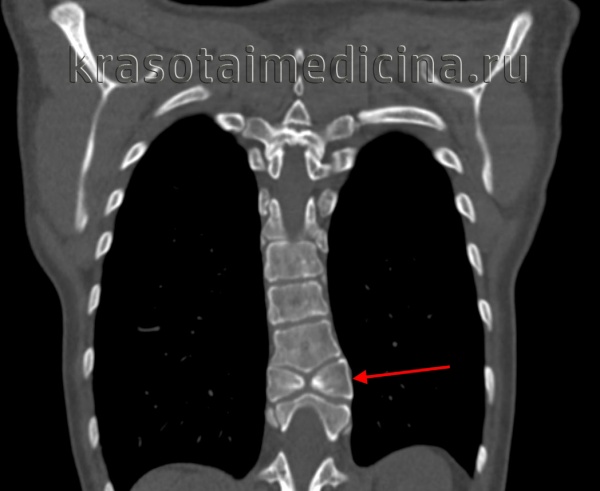

3. КТ признаки нарушения формирования позвонков:

• Костная КТ:

о Сагиттальные или фронтальные дефекты позвонков, полупозвонки, «позвонки-бабочки»:

- По аксиальным срезам очень сложно оценить форму патологического позвонка, в этом отношении намного более информативны сагиттальные и фронтальные реконструкции

о ± дизрафия задних элементов позвонков, аномалии слияния центров оссификации:

- Наиболее информативны в этом отношении аксиальные изображения

о Трехмерная реконструкция КТ-изображений наиболее информативна при осуществлении предоперационного планирования

(Слева) Трехмерная КТ-реконструкция: несбалансированный правосторонний L3 полу позвонок, являющийся в данном случае причиной правосторонней сколиотической деформации. Корень дуги и задние элементы L3 позвонка слева в данном случае представлены рудиментарными фрагментами.

(Справа) На фронтальном Т2-ВИ грудопоясничного отдела позвоночника у пациента со сколиозом обнаружен сегментированный несбалансированный правосторонний L3 полупозвонок. Такая односторонняя несбалансированная конфигурация у данного пациента стала причиной врожденной сколиотической деформации.